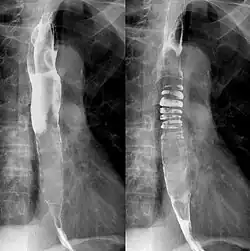

Die Röntgenbreischluckuntersuchung zeigt einen langen, keulenförmigen, umspülten, intraluminalen Tumor mit glatter, etwas gelappter Kontur. Bei einem sehr voluminösen Tumor kann der erweiterte Ösophagus in der Röntgenaufnahme des Thorax für das Mediastinum konturbildend werden.